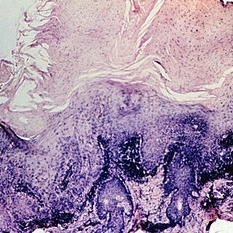

Slide 5-37 Slide 5-37Feb 25 2019 by Lancaster Course in Ophthalmology Edge of squamous cell carcinoma of the skin showing sudden change from normal epithelium to infiltrating islands of large, malignant squamous cells. Condition/keywords: epithelium, squamous cells